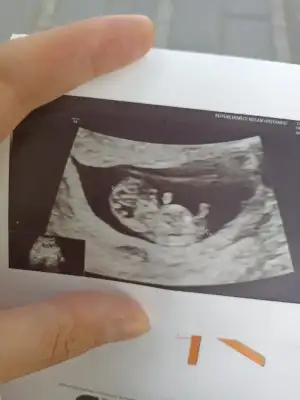

Teyzelerımm ben geldımm. 9+3 günlüğüm. Kalbım dakıkada 174 atıyor 😍🧿 kesem düzgün kanama alanım yok. Ayaklarını bıle gordum kızlar ama burda cıkmamıs. 🧿♥️ Rabbım sen nelere kadirsin 😍🤲🏻 Doktorum banada taramalarla ugrasma dırek nıfty testı yaptır dedı. Arayıp fıyat verecekler bakalım.

• 2492814F-DC4A-4B9E-A527-907F934329BF.webp

2492814F-DC4A-4B9E-A527-907F934329BF.webp

37,9 KB · Görüntüleme: 92